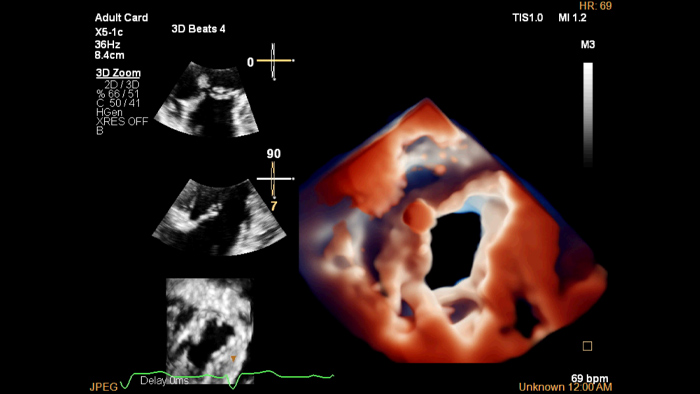

X5-1c TV TrueVue

TrueVue Color

Für eine verbesserte Darstellung der Herzanatomie in der transthorakalen und transösophagealen Echokardiographie erleichtert Philips TrueVue Color mit seiner virtuellen Lichtquelle die Visualisierung von Defekten und die Erkennung der Tiefe innerhalb der Strukturen.